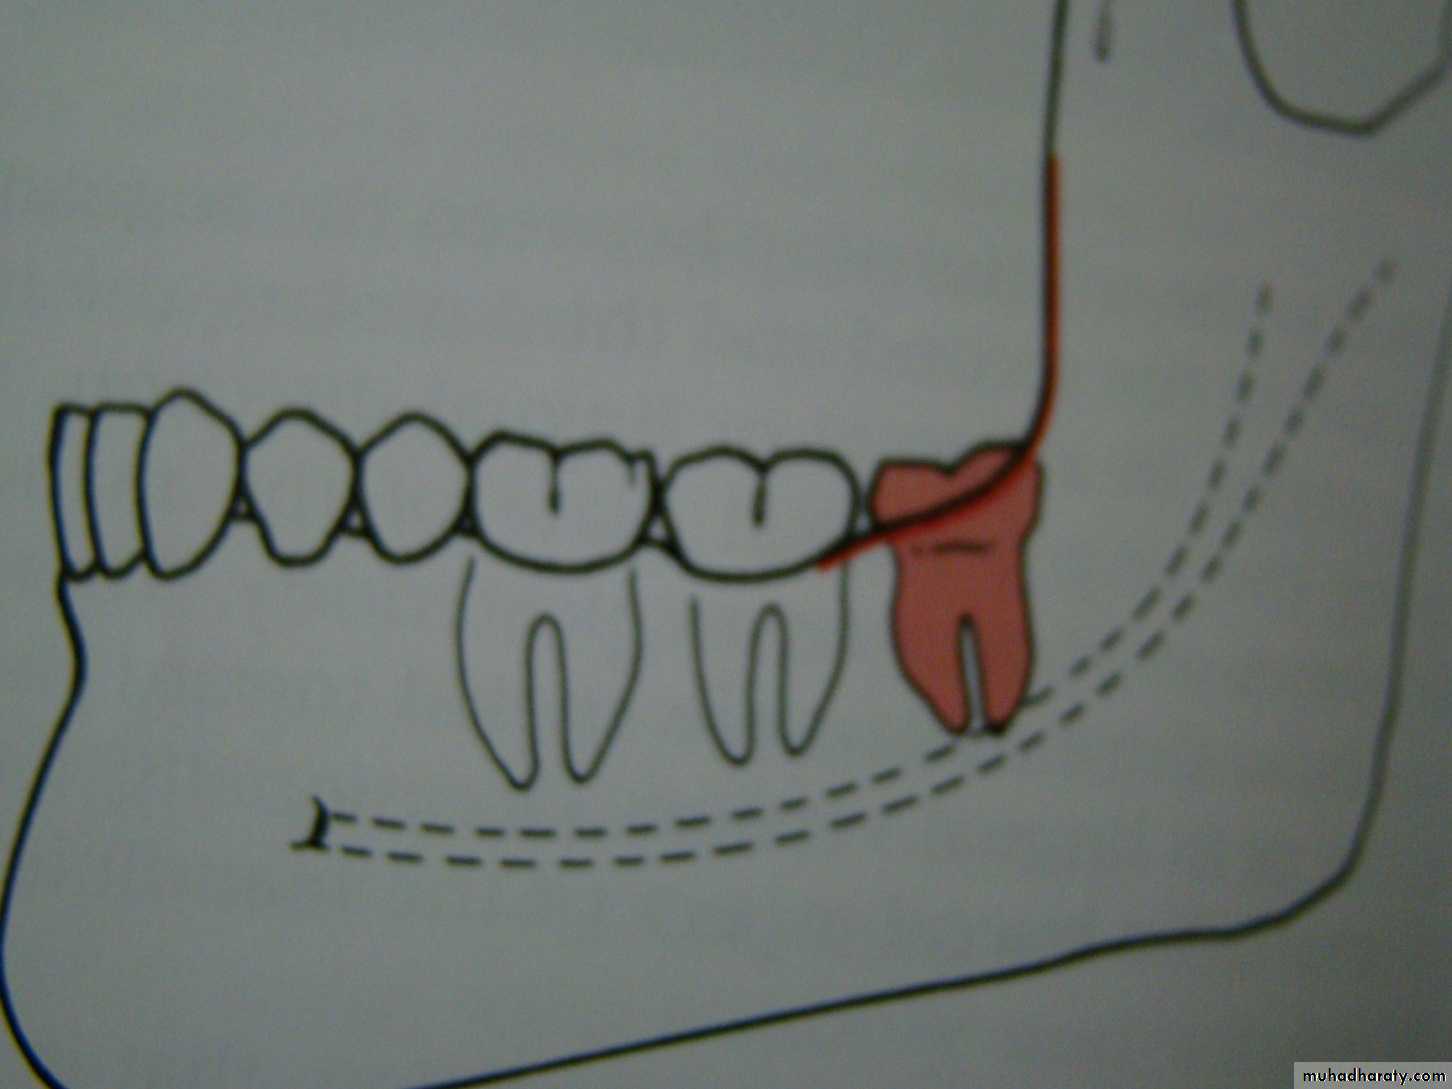

distoangular

1-White line: it is an imaginary line draw along the occlusal surface of erupted first and second molars extend posteriorly over 3rd molar region . Its benefit is to determine the angulations of an impacted tooth and its relationship with occlusal surface of erupted 2nd molar(depth).2- Amber line: It is a line drawn from the surface of bone laying distally to the 8 and to the crest of interdental septum or alveolar septum between 6 and 7. it determine the amount of bone removal

3-Red line : it is draw perpendicular from amber line to an imaginary point of elevator application located mesially to the CEJ except in Disto angular impaction it is distally located . It is used to measure the depth of the impacted tooth.

Note: Any tooth with red line length more than (5 mm) it is better to remove it under G.A.